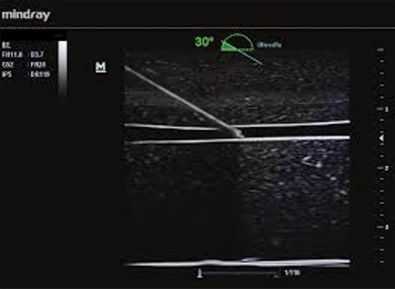

iNeedle - Vylepšenie vizualizácie pomocou ihly iNeedle

iNeedle (kontrastná vizualizácia punkčnej ihly)

iNeedle: Kontrastné zobrazenie bioptickej ihly.

iNeedle: Kontrastné zobrazenie bioptickej ihly.